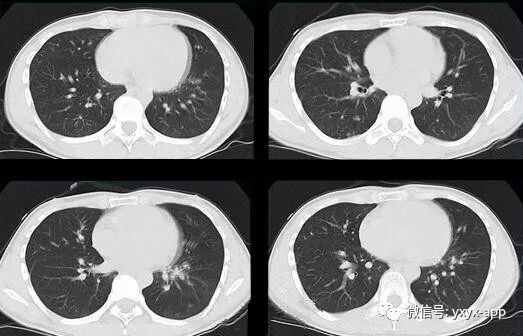

评论:两肺斑片状磨玻璃影,与周围组织分界清楚,呈“地图样”表现,部分病变延伸至胸膜下,部分小叶间隔增厚,气管居中,肺门及纵膈未见肿大淋巴结影,未见胸腔积液。患者青年男性,临床症状轻微影像表现严重,抗炎治疗无效。考虑肺泡蛋白沉积症

1、两肺较淡的斑片状磨玻璃影,不呈叶段分布,病变可延伸至胸膜下,其中磨玻璃影中可见小结节影,磨玻璃影与正常肺组织分界清楚,形成“地图样”改变,这种地图样分布的原因,可能是由于这种斑片影以肺小叶为病变单位,小叶间隔在一定程度上限制了病变的蔓延;

2、由于小叶间隔和小叶内间隔的增厚形成网格状阴影改变,弥漫的磨玻璃影及其内部的网格小叶间隔增厚形成了“铺路石样”改变;

3、实变区具有多样性,多种不同程度的病变共存,病灶内可见支气管气像;

4、病变部位以肺门及双下肺明显。